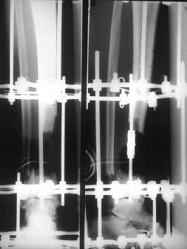

Огнестрельный дефект костей и передней группы мышц, поступил с юнилатеральным аппаратом, стабильность плохая, из раны обильное гнойное

отделяемое. #1;#2. Стержневой апп. снят, наложен апп. Илизарова, дренажно-ирригационная система промывки раны. #3; #4. После стихания инфекции,